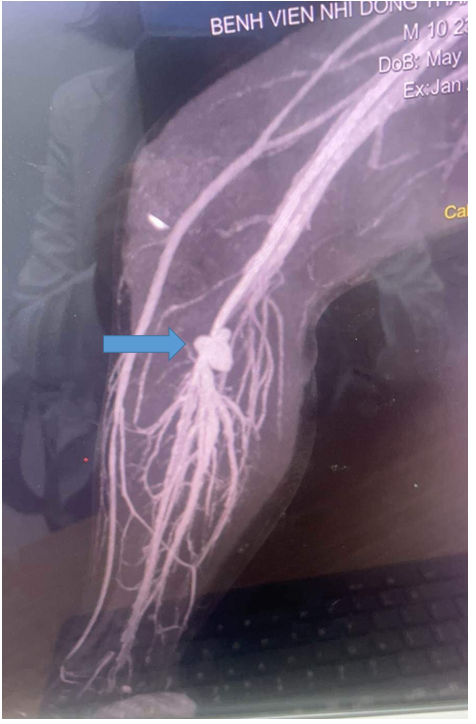

Kết quả CT scan cho thấy phình mạch máu, gây cản trở tưới máu chi của bệnh nhi. (Ảnh: Bệnh viện cung cấp)

Tại bệnh viện, bệnh nhi tỉnh. Các bác sĩ đã thực hiện siêu âm, chụp CT scan ghi nhận bệnh nhi bị hẹp đoạn cuối động mạch khoeo, kích thước tại vị trí hẹp 2,5mm; tắc đoạn cuối tĩnh mạch… nguy cơ đoạn chi nếu không phẫu thuật kịp thời.